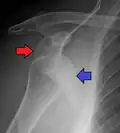

A Hill–Sachs lesion is an impaction of the head of the humerus left by the glenoid rim during dislocation.[6] Hill-Sachs deformities occur in 35–40% of anterior dislocations. They can be seen on a front-facing X-ray when the arm is in internal rotation.[11] Bankart lesions are disruptions of the glenoid labrum with or without an avulsion of bone fragment.[12]

Anterior dislocation of the right shoulder. AP X ray -